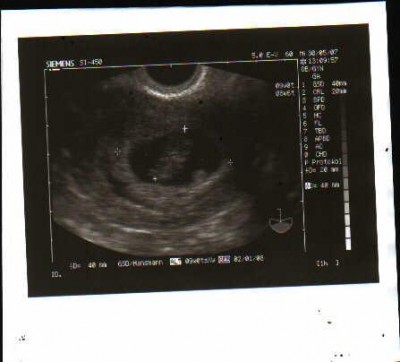

naja freuen kann ich mich noch nicht so richtig über die schwangerschaft.. noch wissenw ir ja nicht ob sie auch intakt ist

das macht mir schon noch recht sorgen...denn die letzten beiden Schwangerschaften waren ja nicht gerade von erfolg gekrönt

daher freu ich mich momentan über jeden mensfreien tag...aber mehr ist noch nicht drin...denn wer weiss ob die zwei tigerchen auch wirklich in der GM sitzen und es sich dort gemütlich gemacht haben???